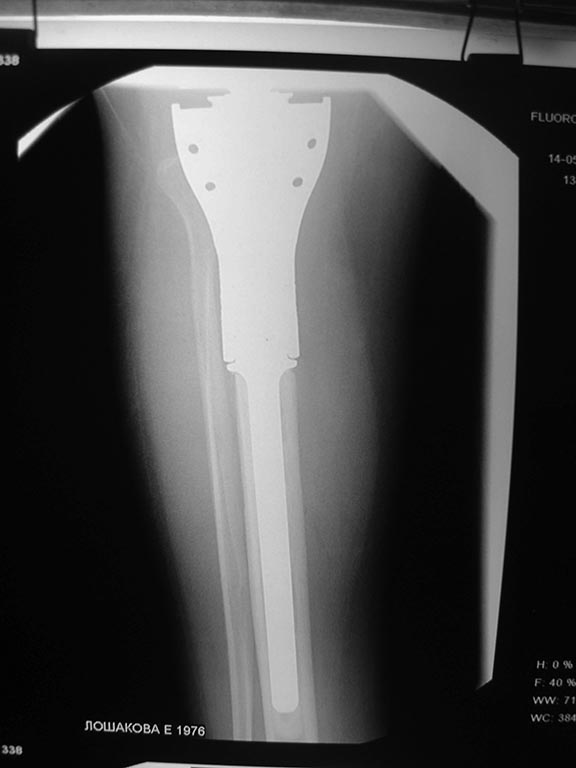

Уважаемые коллеги помогите с дальнейшей тактикой лечения.Больная 1976 г.р оперирована в октябре 2012 по поводу остеобластокластомы проксимального метафиза пр.большеберцовой кости модульным имплантом stryker

послеоперационное течение гладкое.Ходит с полной нагрузкой.Незначительно прихрамывая на пр.ногу .П/о рубец до 20 см без признаков воспаления Пальпаторно по передней поверхности метаэпифиза ю/берцовой кости .Активного разгибания нет ,и собственная связка надколенника не контурирует.Пассивные движения в полном обьеме.На контрольных рентгенограммах признаков нестабильности нет.В течении последних трех недель появилось по передней поверхности пр.голени серома.Пунктирована несколько раз – прозрачная синовиальная жидкость.Взята на посев –чуствительна к гентомицину,цефазолину ,цефтриаксону и левофлоксацину.В настоящее время получает цефазолин 1.0 в/м 3 раза и гентомицин 160 мг в/м 1 раз.(уже 5 дней)Динамики нет, жидкость продолжает скапливаться примерно в том же обьёме.